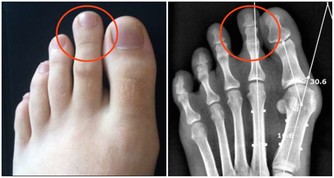

*****4、 尿頻:*****

腎虛會引起尿頻,尿頻是腎陽虛證的症狀表現之一。腎陽是一身陽氣的根本,腎陽不足,會使膀胱氣化功能異常,出現小便量多,尿頻的表現,尤其是在晚上時,小便次數會更多。